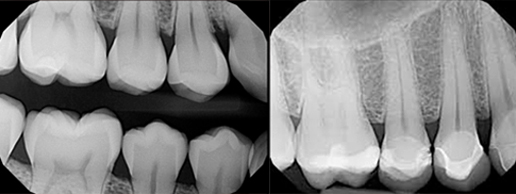

Radiologie numérique avec radiation minime:

Capteurs radio intra oral

La radiologie numérique permet un diagnostic très précis pour un traitement plus efficace!

Ce type de radiologie comporte plusieurs avantages :

Radios intraorales numériques